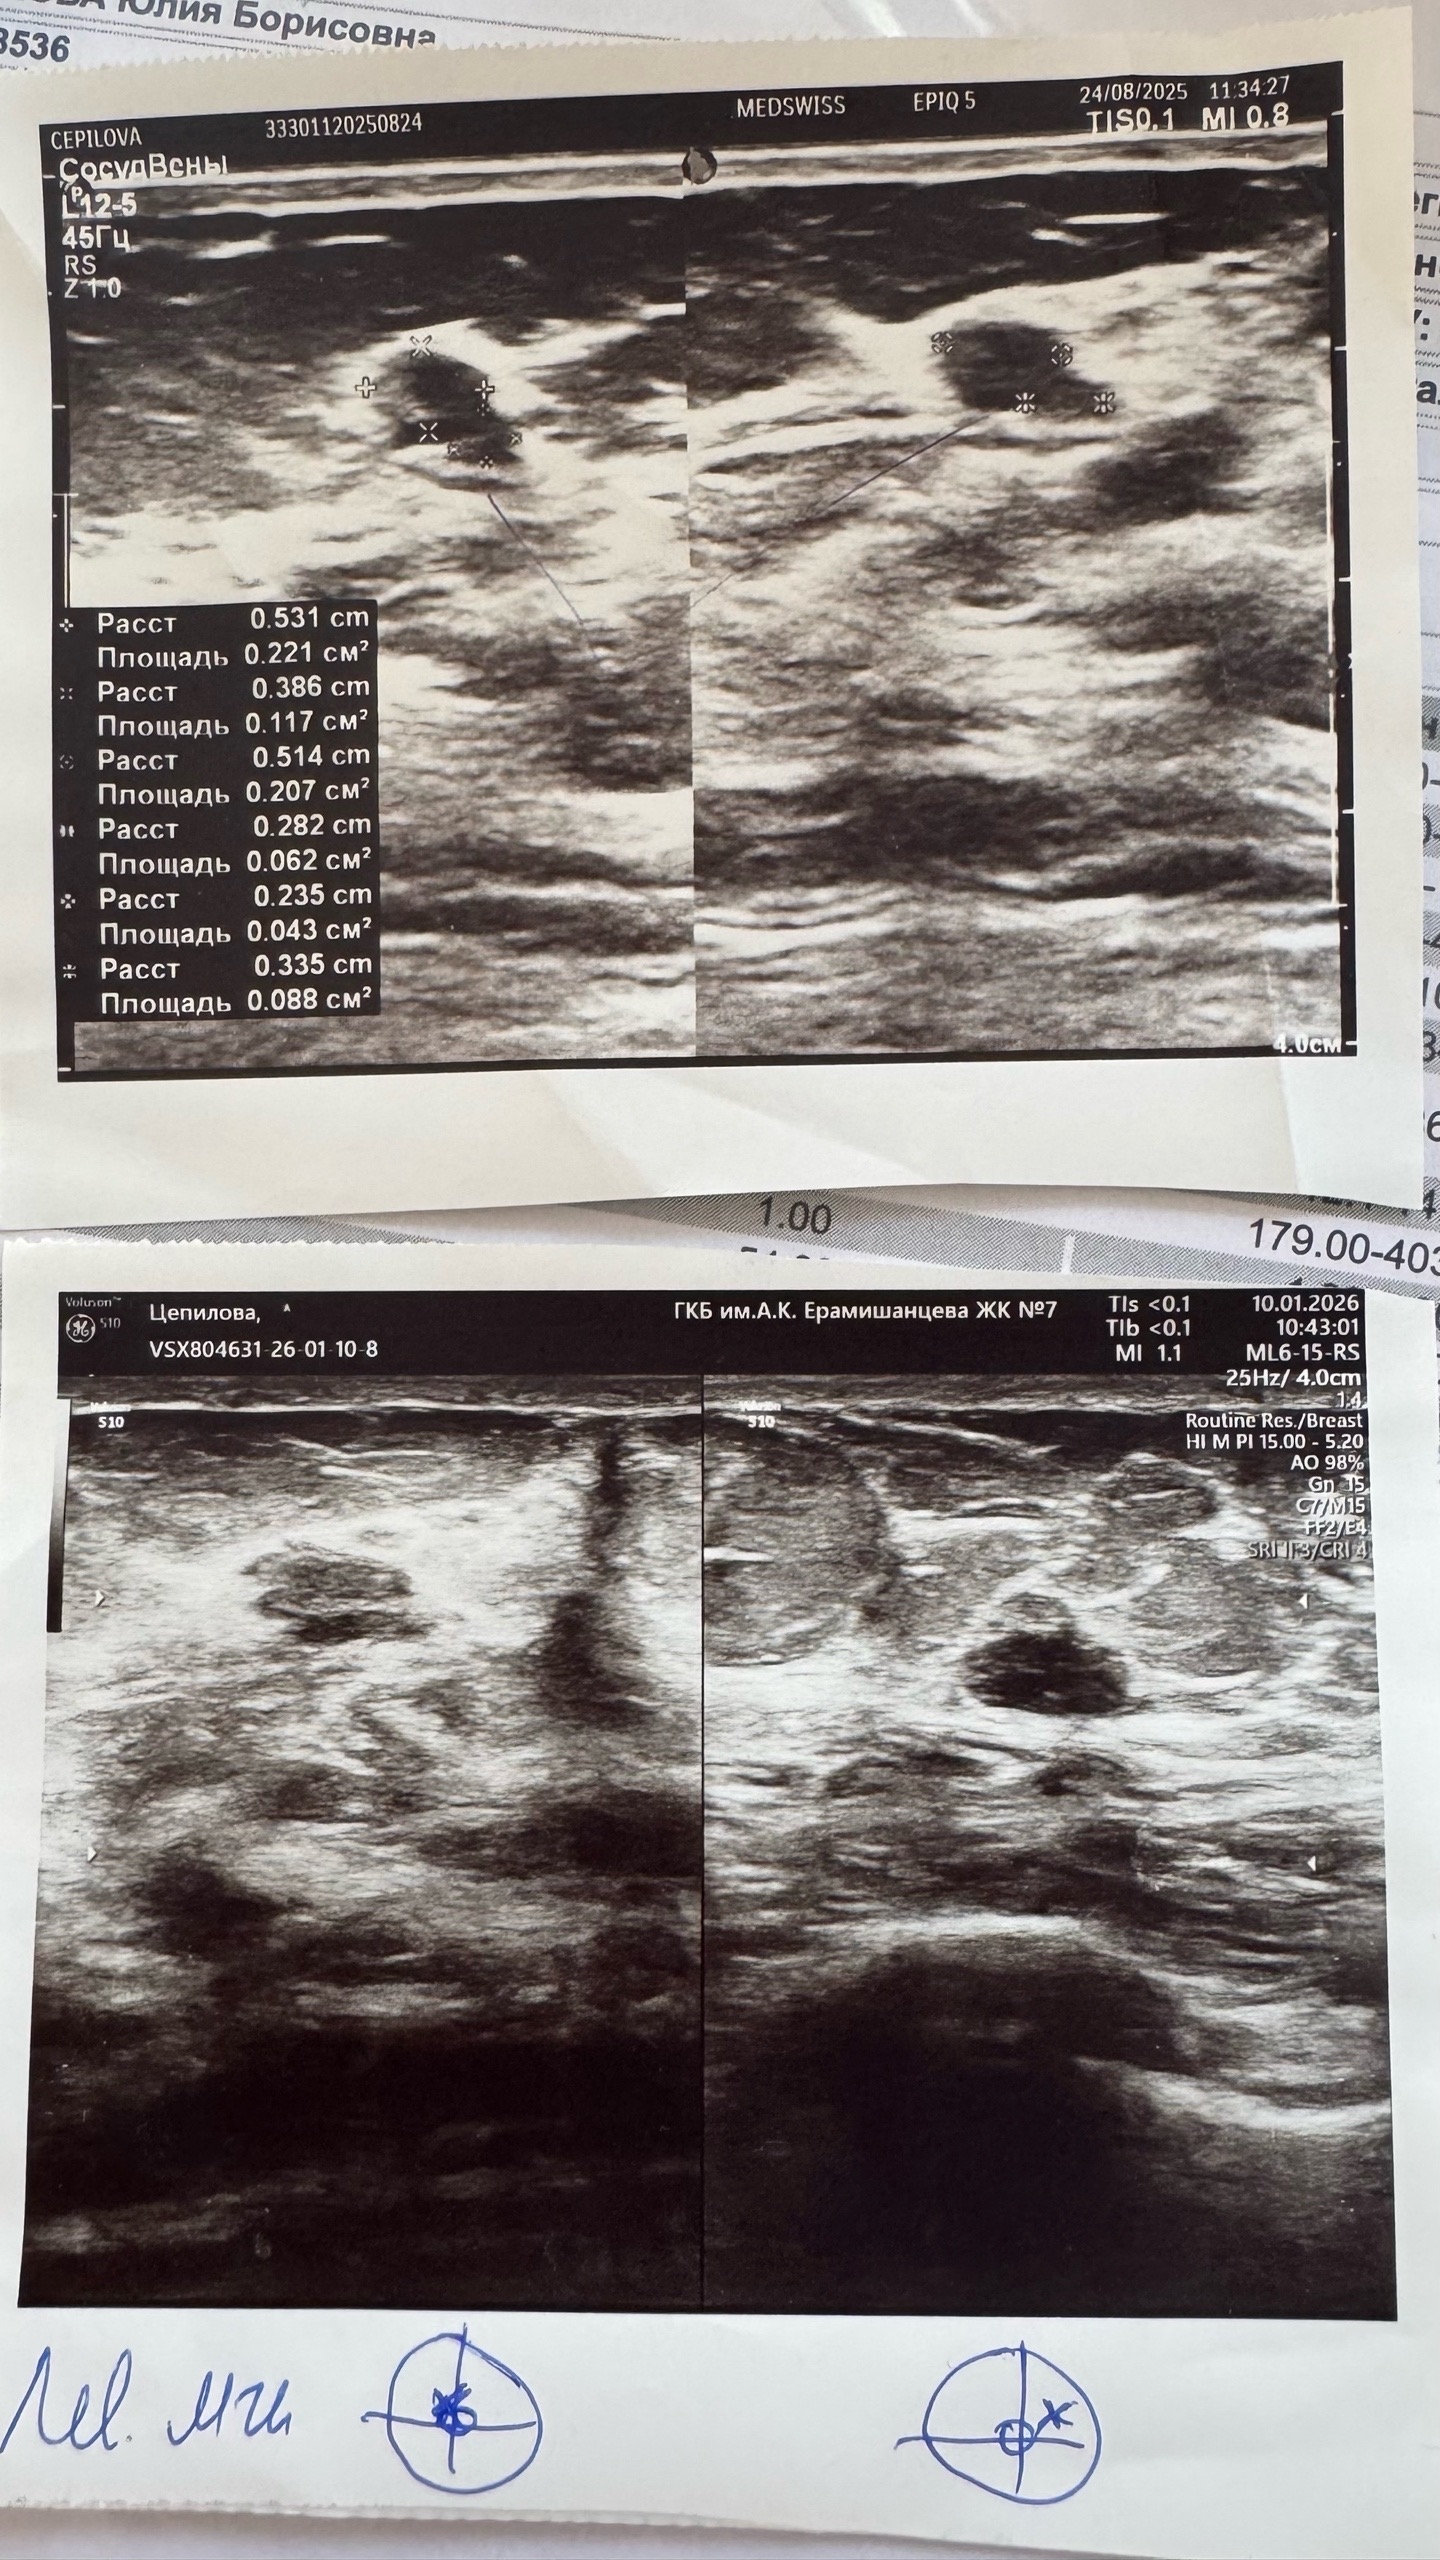

На плановом узи мне сообщают, что нужно сходить к онкологу. Ставят BIRADS 3 (предположительно доброкачественно) и в заключении пишут, что 2 образования аналогичных размеров. Я пугаюсь и начинаю пересматривать старые заключения узи и выясняю, что уже на двух последних узи у меня было 2 образования, но я ввиду частого посещения врача уже не сильно внимательно просматривала результат, слишком опрометчиво доверяя врачам. Мне ничего не говорили и я не вчитывалась. Меня окутал липкий страх, так как я поняла, что за полгода у меня выросло образование в 1 см.

Бегу к тому же врачу, кто делал мне трепан-биопсию. Это платная клиника, врач пугает меня и говорит что срочно надо делать трепан биопсию. Мне выставляют 23000 за трепан-биопсию 1 образования, то есть 46 000 за исследование. Я напрягаюсь и решаю пойти еще в Логинова по ОМС (мне дал направление гинеколог из женской консультации Ерамишанцева). Итак, в Логинова врач проводит короткий осмотр и отправляет меня на пункцию (ТИАБ) по ОМС двух образований. Делают оперативно (проводят в 6 корпусе на 1 1 этаже, гораздо более щадяще чем при трепан-биопсии) и уже на следующий день готов результат — "нет признаков злокачественной опухоли в пределах материала". Здесь я начинаю сомневаться, так как врач при проведении пункции говорит "надеюсь там будет что-то понятно, тк образование объемное, надо бы делать трепан-биопсию". Теперь я в страхе, что пункция не информативна и могли пропустить рак.

Бегу по записи к врачу-онкологу, он говорит что эти образования будут расти скорее всего, так как я планирую беременность (на момент действий мне 34 года). Это сулит лактостаз и операцию в любом случае. Лучше удалять. Также хочу отметить, что с 2024 года я заметила изменение риторики — раньше мне врачи говорили наблюдать, теперь все говорят "удалять, так как фиброаденомы могут перерождаться в рак". Но напомню, удалять по ОМС бесплатно можно только доброкачественые образования от 2 сантиметров. Но я уже настолько напугана, что хочу немедленно избавиться от них и уже получить гарантированный ответ, что за опухоли?! Так как у меня до сих пор не диагноза (мне нигде не пишут что это. Просто "нет атипии", а образования есть. Грудь болит, беспокоит. Записываюсь на ближайшую консультацию по вакуумно-аспирационной биопсии в Логинова по направлению от онколога.